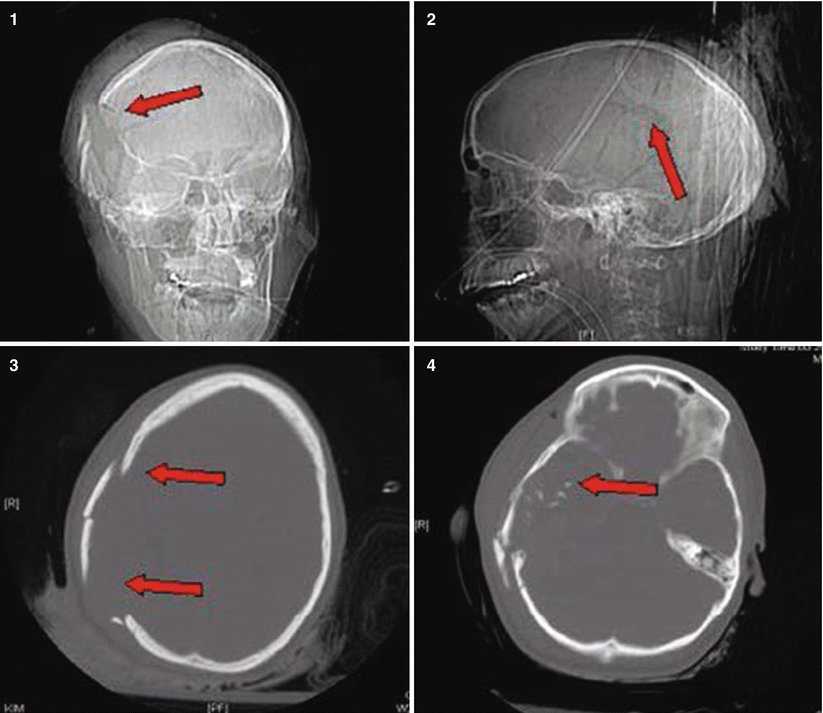

Fig. 27.2

Patient No. 2: a 23-year-old female, who sustained a solitary GSW to the head from close range. Entry wound on the R cheek, exit wound R parietal. Arrows in plates 1 and 2 of this figure illustrate the blow out fracture of the right sided calvarium as seen on CT scout images; This creates a hemispheric decompression. Arrows in plate 3 and 4 indicate the corresponding bony defect with multiple fragments as seen in bone windows of the axial CT scan. Arrows in plates 5 and 6 indicate the hemorrhagic contusion and SAH. Arrows in plates 7 and 8 indicate the hemicraniectomy site (7) and evacuated subdural hematoma site (8). Arrow in 9 points at the inserted hemicranioplasty allograft.Arrow in 10 points at the cystic portion of the encephalomalacia from the bullet tract